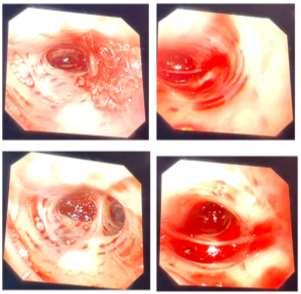

bronchoscopy. It showed active bleeding in the left bronchus (Figure 2) and no bleeding in the right bronchus. Careful examination revealed that the location of the breach was on the lateral wall of the left lower bronchus. In order to avoid contaminationoftherightlung,wereplacedtheregularsingle lumen endotracheal tube with a 32 left-sided double-lumen endobronchial tube. After a consultation with the thoracic department,wedecidedtoperformleftlowerlunglobectomy. The procedure was completed while rewarming. The separation from CPB went smoothly and the patient was send to ICU after the surgery.

Figure 1: CT showed the mass in the left pulmonary artery. Figure 2: Fiberoptic bronchoscopy showed active bleeding in the left bronchus.

Postoperative fiberoptic bronchoscopy in ICU showed that the mucosa of the left upper lobe was obviously congested and edematous, and the bronchus of the left lower lobe was blocked. There was no obvious abnormality in the segments and mucosa of the right lung. The tracheal intubation was removed on the 3rd postoperative day (POD). The patient returned to the general ward on the 4th POD and was discharged in a stable condition on the 9th POD.